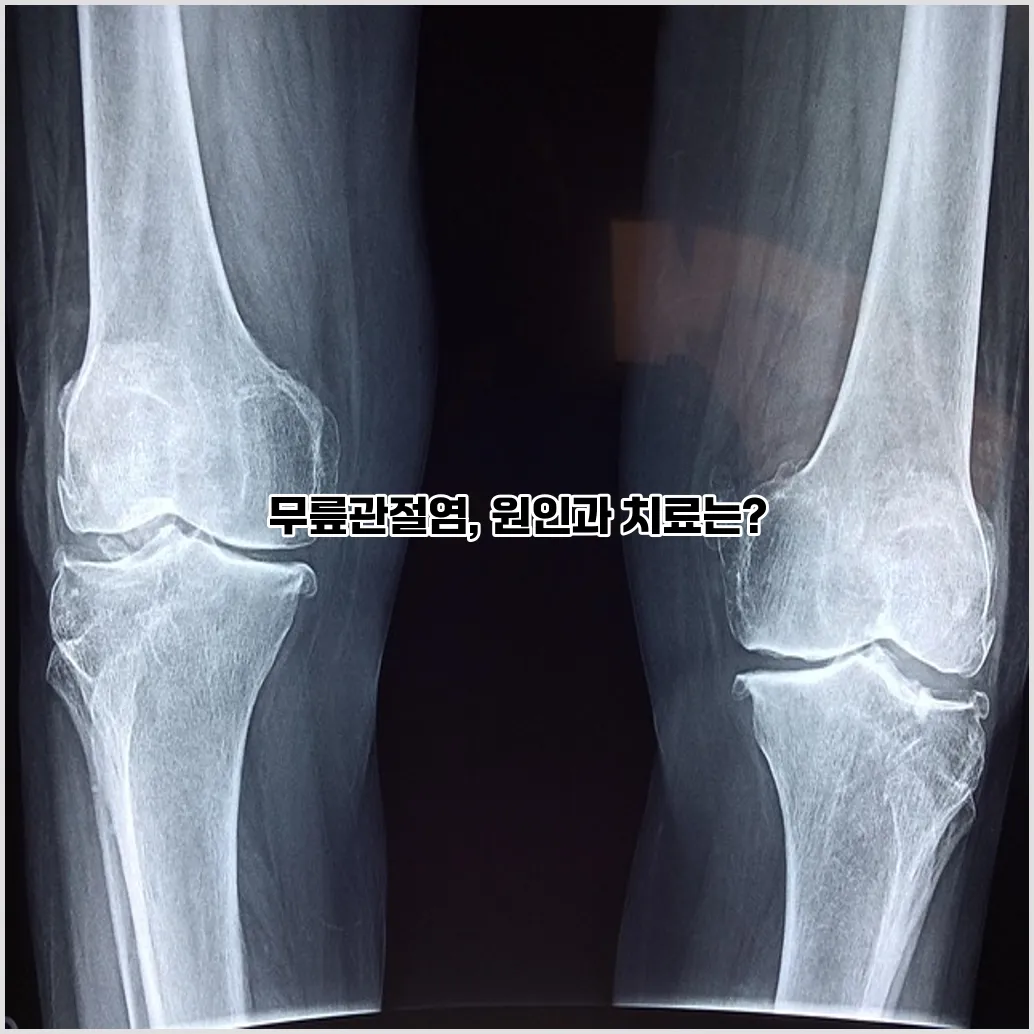

임상 검사와 함께 영상진단이 기본적인 정밀 검사의 도구로 활용됩니다. 가장 흔히 사용되는 영상기법은 X선 촬영으로, 관절 간격의 좁아짐이나 뼈 돌기(뼈융기), 또는 뼈의 변형 등을 확인할 수 있습니다. 필요시에는 MRI(자기공명영상) 검사를 통해 연골, 인대, 연부조직 등 더 상세한 관절 내부 상태를 관찰할 수 있습니다. 이와 같은 영상진단은 관절염의 정도를 파악하고, 맞춤형 치료 계획을 세우는 데 매우 중요하며, 조기 진단으로 더 적절한 치료를 받을 수 있도록 돕습니다.

무릎관절염은 병력청취와 신체 검사를 통해 의심할 수 있으며, X-ray 촬영이 가장 일반적으로 사용돼 관절의 연골 손상 정도와 관절 간격을 평가합니다. 필요에 따라 MRI 검사를 통해 연골, 인대, 연부조직 상태를 보다 정밀하게 확인할 수도 있습니다. 혈액 검사나 관절액 검사도 감별 진단에 활용됩니다.